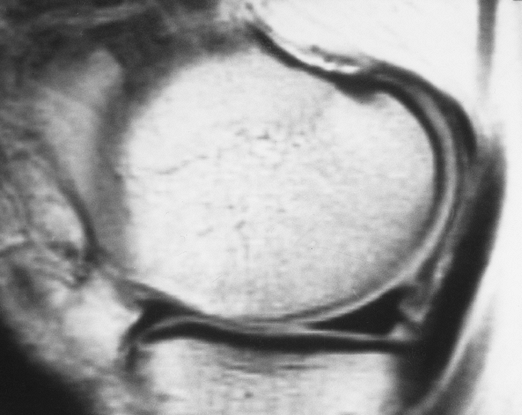

FIGURE 5-24 Coronal fat-suppressed T2-weighted image of a bucket-handle tear of the medial meniscus. Note truncated meniscus (arrow) and displaced fragment (open arrow) giving a “double posterior cruciate ligament (PCL)” sign. There is also a complex tear of the lateral meniscus (small arrow).